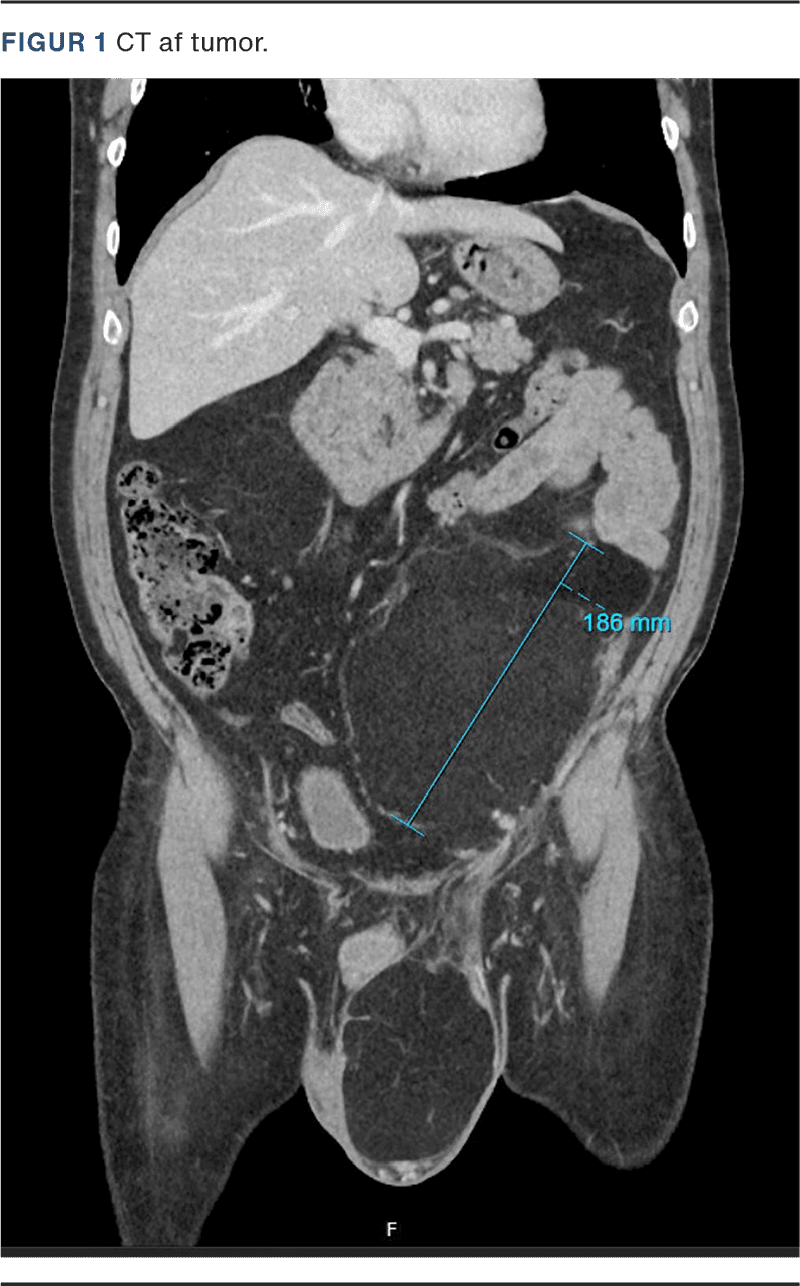

Patienten blev udredt med CT, hvor man fandt en stor tumor i venstre hemiskrotum samt i retroperitoneum. Tumoren kommunikerede via ingvinalkanalen og strakte sig op mod venstre nyre (Figur 1).